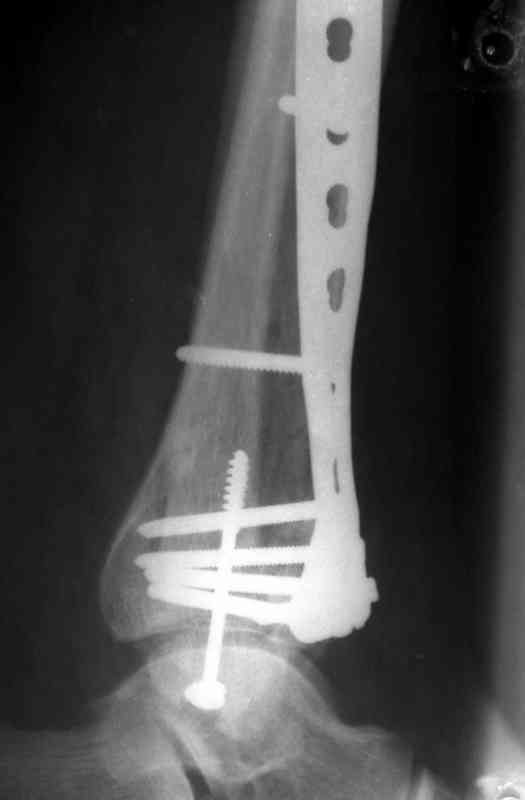

На рентгенограммах типичный перелом пилона по типу С-3. есть опыт до 100 открытых опреаций у нас в клинике. 20 примерно в год. Принцип один -все внутрисуставные переломы нуждаются в открытой репозиции и внутренней стабильной фиксации. При поступлении КТ не надо, так как получается только нагромождение костей. Истинной картины нет. Главное восстановить длину малоберцовой кости - это ключ к успеху. При поступлении меньше всего надо думать о сосудистых расстройствах, т.к. сама операция и репозиция даже сначала частичная даёт улучшение сосудитых нарушений. Причём очень быстро. Операция в 2этапа. При поступлении доступ позади наружной лодыжки, причём обязательно. После этого репозиция малоберцовой кости и фиксация пластиной 1/3 трубки под винт 3,5. Дренаж и любой аппарат наружной фиксации. Затем после спадения отёка на 5-7-10 день аппрат снимается и дугообразный разрез спереди от медиальной лодыжки 10-12 см. Главной чтобы расстояние между 1 и вторым разрезом было не меньше 7-8 см. Тогда не будет некрозов лоскутов. Таранная кость используется как матрица на неё укладываются отломки и фиксируются пицами. Ренг-контроль. Отломки лежат все отдельно, но ничего не высыпется. При переломах С-3 всегда нужна костная пластика (из крыла). Фиксация пластиной лист клевера простой или LCP. Гипс не нужен. Дренаж до 48 часов. Операция длится 3-4 часа обязательно без жгута. Посылаю примерно такой же случай.

Посылаю результат лечения предыдущего больного через год.